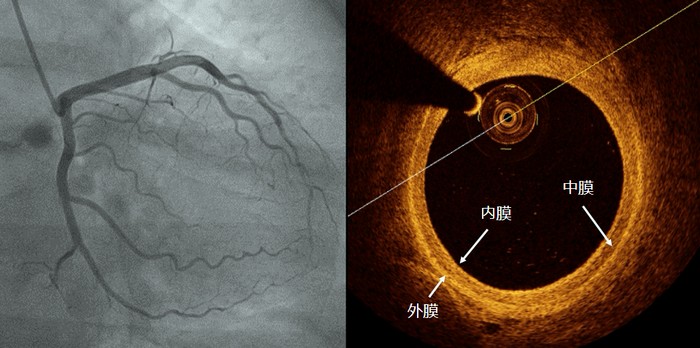

由于OCT的光纤探头很小(比牙签的头端还细),可以放入到血管腔内,同时能实时360°从内部观察血管壁的情况,获得血管内部的图像信息,故有“活体显微镜”之称。它能清晰地显示动脉的内膜、中膜和外膜三层结构。